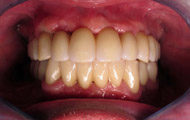

Exemple d’une réhabilitation complète implantaire

Situation clinique terminée